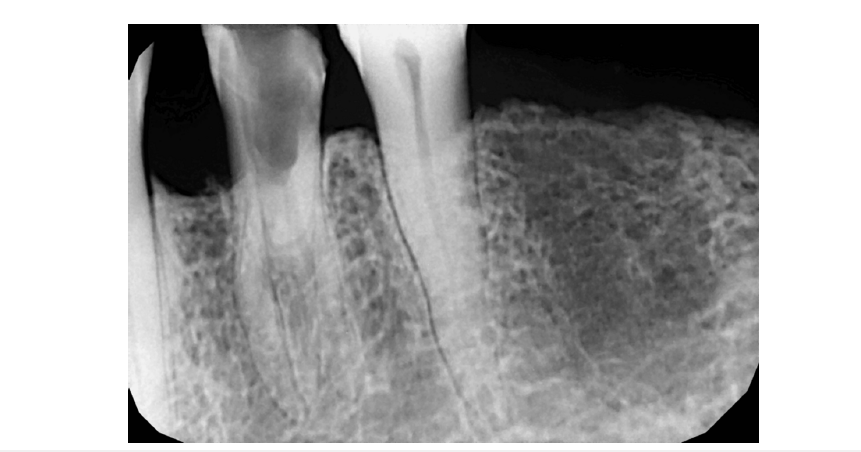

A 67-year-old Indian female patient reported to Parvathi Dental Care Centre, Chennai with a history of severe pain in the lower left side tooth region for the past 2 days. She gave a past dental history of pain present 2 months back wherein she had visited a dentist and a restoration done in the aforementioned tooth. Upon examination, any systemic abnormalities were ruled out and the vitals were normal. Intra oral examination revealed that there was a fractured restoration in relation to tooth#34 and the tooth was highly tender on percussion. She also gave a history of severe tooth pain which aggravated in the supine position. Pain relieved for few hours with medication and comes back spontaneously after few hours. Intra-Oral Periapical Radiograph (IOPAR) was taken with radio visiography (KaVo Gendex GXS-700 Sensor, KaVo Dental, Charlotte, North Carolina, United States of America) and clearly revealed that the cavity preparation was extensive and encompassing into the pulp chamber. IOPAR also revealed variation in the radicular anatomy unusual to this tooth (Figure 1). Case discussion was done with the patient and root canal therapy was initiated after obtaining written consent from the patient.

Figure 1:Pre-operative radiograph of mandibular left first premolar (tooth #34) showing a radiolucency involving enamel, dentin and pulp suggestive of extensive cavity preparation done. The root morphology of the tooth was indicative of presence of multiple roots.